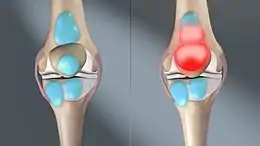

Bursitis is inflammation or swelling of one or more fluid filled sacs known as bursae.[3] These sacs are lined with a synovial membrane that produce a lubricating synovial fluid.[4] With bursitis there may be difficulty moving, tenderness, and pain in the area affected.[1] With bursitis of gradual onset pain may be absent.[3] Complications may include septic bursitis.[2]

Causes of bursitis include overuse, infection, trauma, and inflammatory disorders.[3] There are more than 150 bursae in the human body.[4] The most commonly affected are the prepatellar, olecranon, trochanteric, and retrocalcaneal.[2] The bursae are at locations where muscles, tendons, and other tissues slide across prominent areas of bone.[1] Normally they function to improve movement between tissues.[3] Diagnosis is generally based on symptoms and examination and may be supported by additional testing.[2][3] Other causes of similar symptoms include arthritis, fractures, tendinitis, and nerve problems.[2]

Bursitis commonly affects superficial bursae. These include the subacromial, prepatellar, retrocalcaneal, and pes anserinus bursae of the shoulder, knee, heel and shin, etc. (see below).[4] Symptoms vary from localized warmth and erythema[4] to joint pain and stiffness, to stinging pain that surrounds the joint around the inflamed bursa. In this condition, the pain usually is worse during and after activity, and then the bursa and the surrounding joint becomes stiff the next morning.